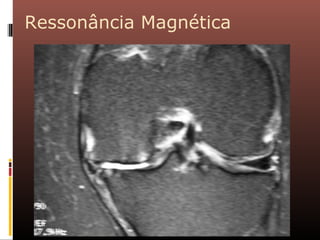

Ressonância Magnética

A ressonância magnética vem sendo cada vez mais

utilizada para aprimorar o diagnóstico por imagem da

osteoartrose. Além de não utilizar radiação ionizante, é

um método mais sensível que a radiografia convencional

na identificação de osteófitos, perda cartilaginosa e cistos

subcondrais, além de detectar anormalidades de meniscos

e ligamentos.

Apesar das vantagens, trata-se de um método caro e

ainda pouco disponível, o que limita sua utilização mais

rotineira.